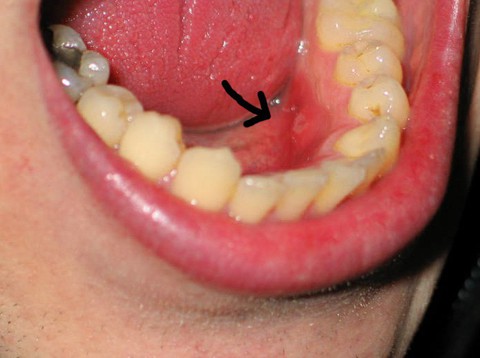

Ảnh minh họa. Nguồn: diseaeseshow.com

Có nhiều triệu chứng có thể gợi ý ung thư khoang miệng. Trong số đó, triệu chứng sớm và thường gặp nhất là những vết loét không liền ở lưỡi, sàn miệng hoặc niêm mạc má. Các vết loét này có thể đau, chảy máu nhưng trong một vài trường hợp có thể không gây khó chịu gì. Khi tổn thương lớn lên mới xuất hiện thêm nhiều triệu chứng như xuất hiện đau hoặc đau tăng lên, nuốt đau, đau tai, thay đổi giọng nói, không phối hợp được động tác nuốt hoặc xuất hiện hạch cổ. Điều quan trọng mà các bạn cần nhớ là một vết loét ở trong miệng dù cho có liên quan với chấn thương hay bệnh viêm loét miệng nếu sau 3 tuần không khỏi, bạn nên đến khám tại cơ sở y tế chuyên khoa về ung bướu để bác sĩ đánh giá tổn thương đó có phải là ung thư hay không.